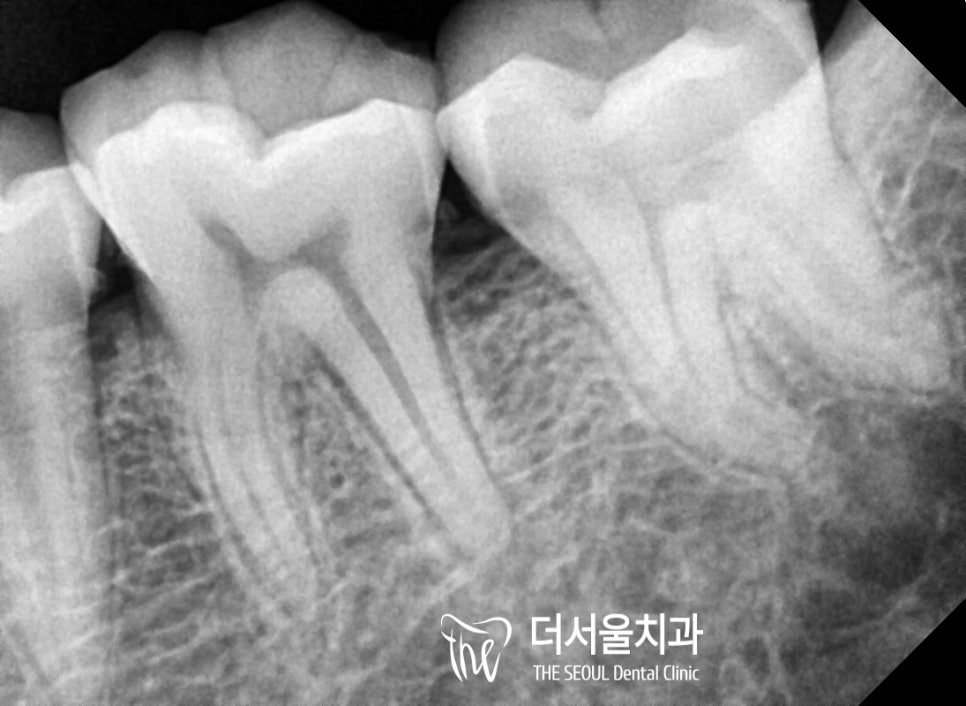

방사선 촬영을 통해 눈에 띄지 않는

내부를 확인해 본 결과,

치수강 근처까지 감염된 것이 확인이 되었습니다.